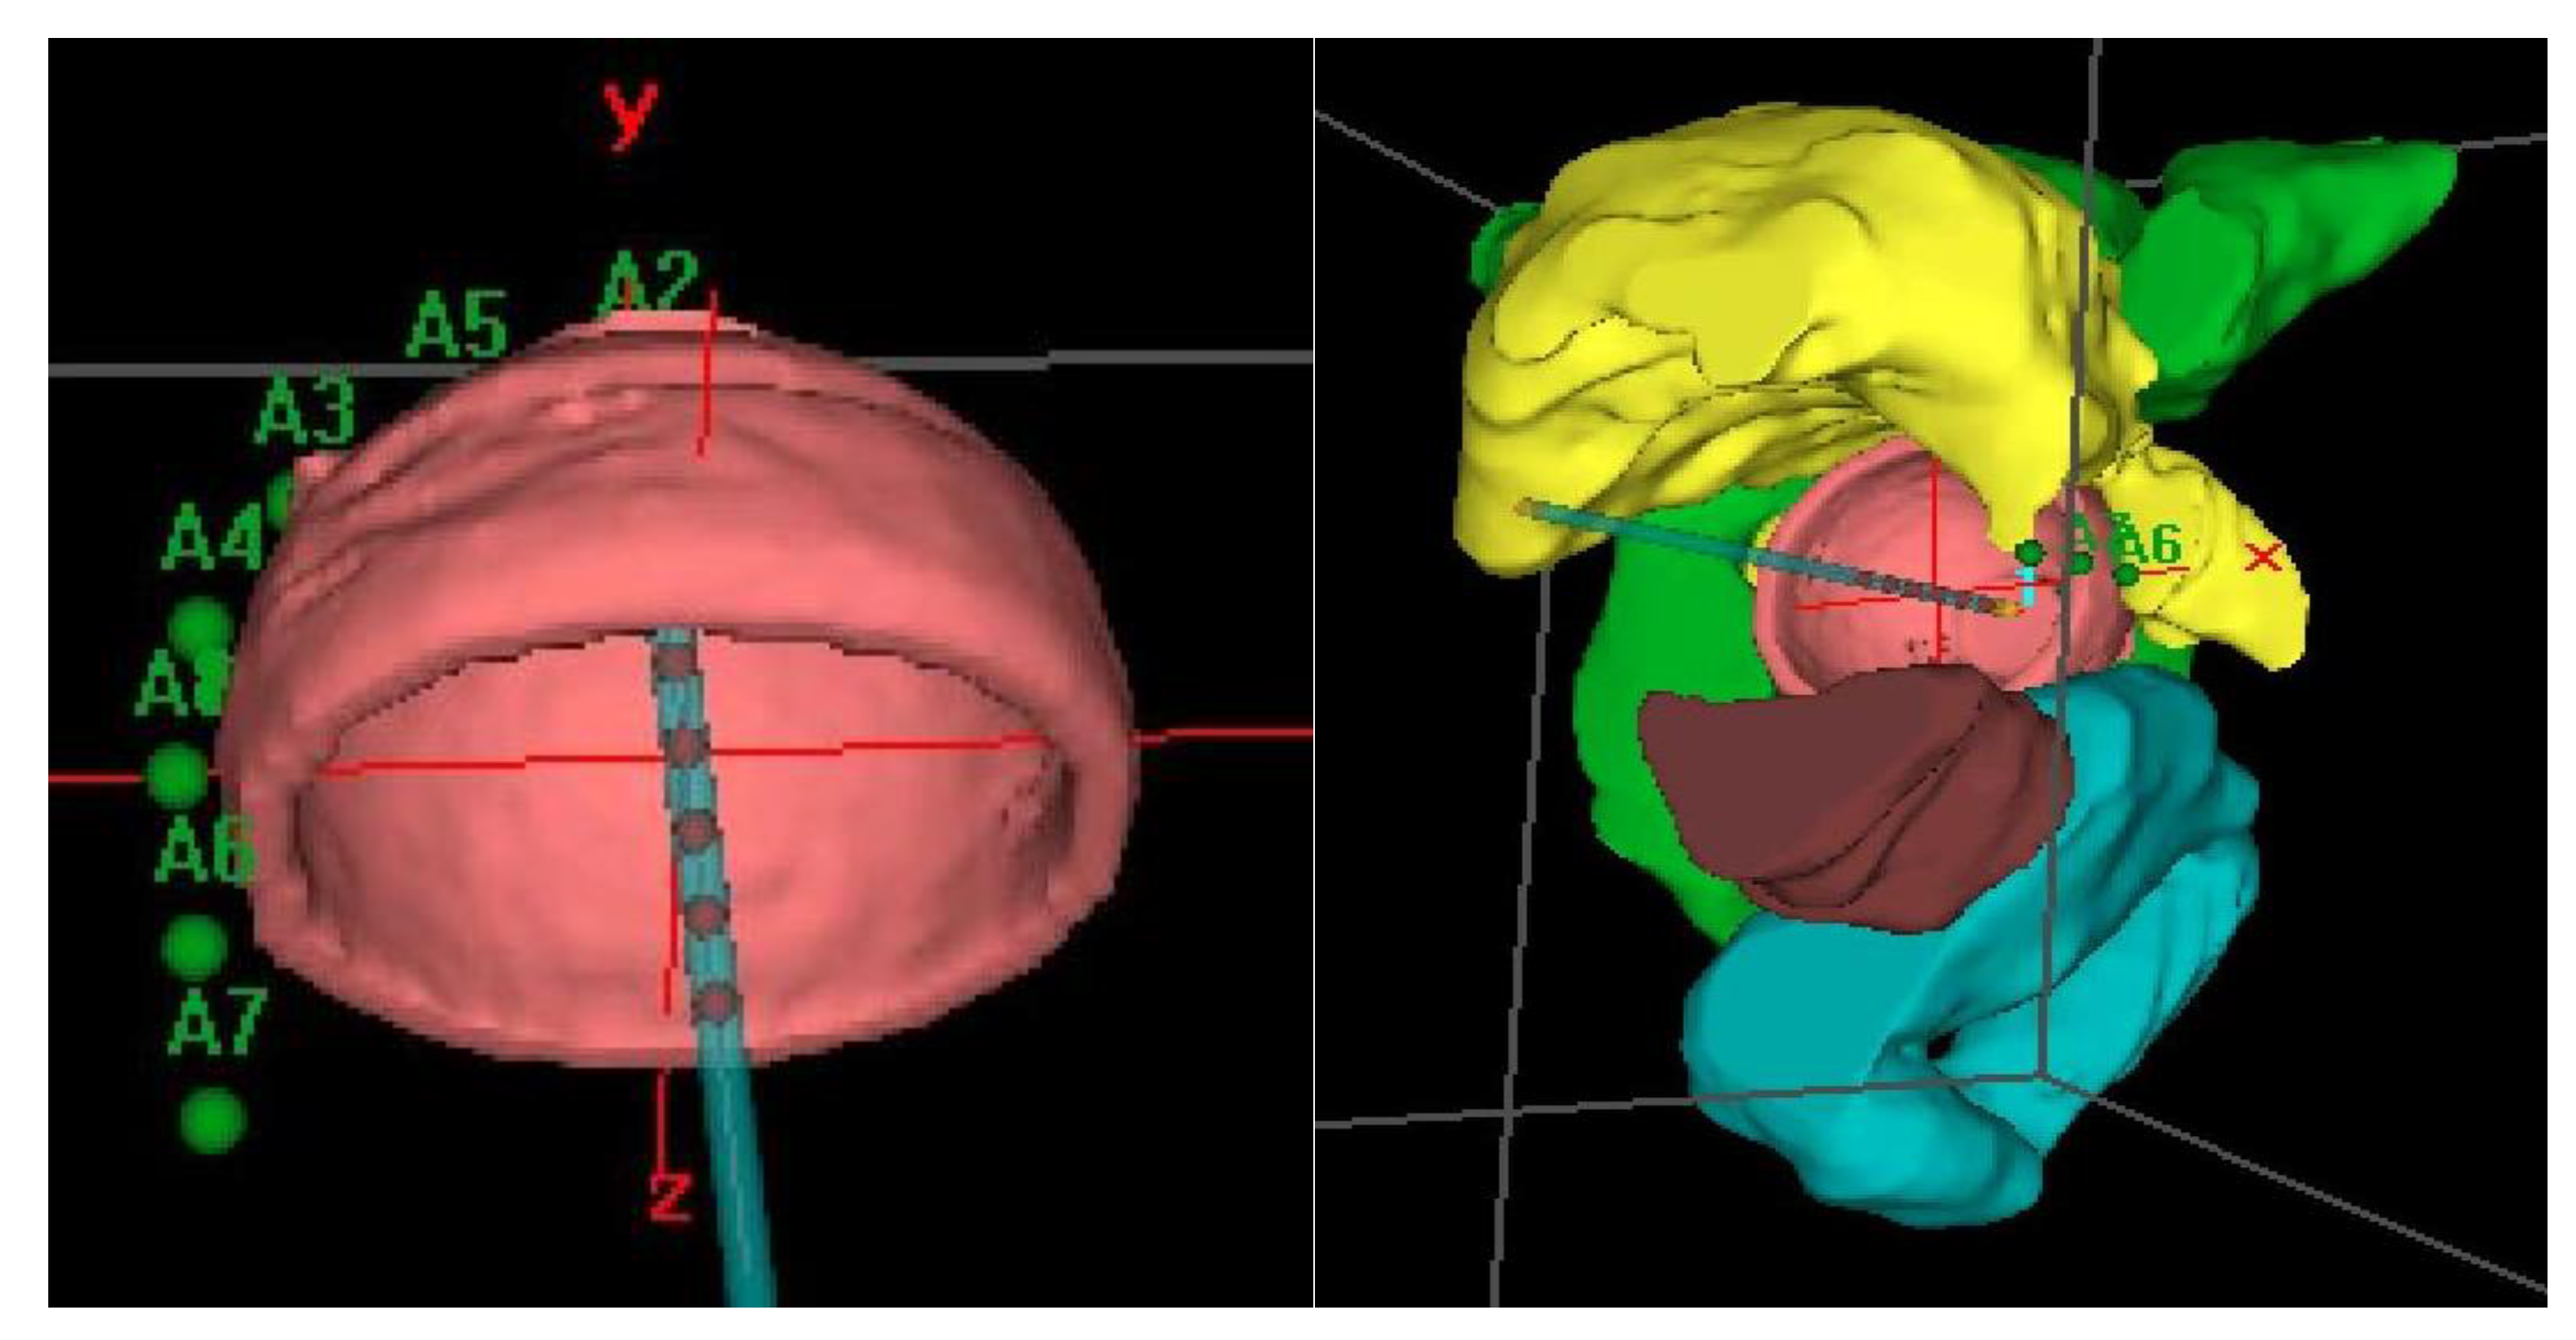

The dose was prescribed at a depth of 5 mm from the applicator surface, and point dose optimization based on distance was used. The active treatment length was 2.5 cm. In the present study, 90% of the isodose surface included the CTV. The voxels corresponding to the vaginal D2cc are always located in a small volume at the top of the vaginal-cuff and any reduction in the dose at this level will consequently reduce the dose at the prescription point. This 2cc volume is described and presented in Figure 3.

Distension of the rectum and air gaps have no impact on the D2cc of vagina considering that the 90% isodose always includes the CTV. The minimum dose of 90% received by 90% of the hottest CTV volume (D90) and the percentage of CTV coverage were calculated as well as the dose to the most exposed 2 cm3 of the rectum, bladder, and vagina. An EQD2(α/β = 3Gy) constraint of 65Gy for rectum and 80Gy for bladder were applied but were never necessary. Dose distribution was not modified to exclude the organs at risk from the dose prescription area. Figure 2 shows the dosimetric study with the area of the vagina most exposed to the dose. After dosimetric evaluation patients underwent treatment with an HDR microSelectron v2 Iridium 192 source and an afterloading source projector (Nucletron® microSelectron V3 digital ELEKTA, Holland, The Netherlands).

Figure 3. Example of dosimetric study showing the most exposed 2 cm3 of vagina to the dose in coronal (a), sagittal (b) and axial (c) planes and (d) dose volume histogram.

Cancers 12 03059 g003aCancers 12 03059 g003b